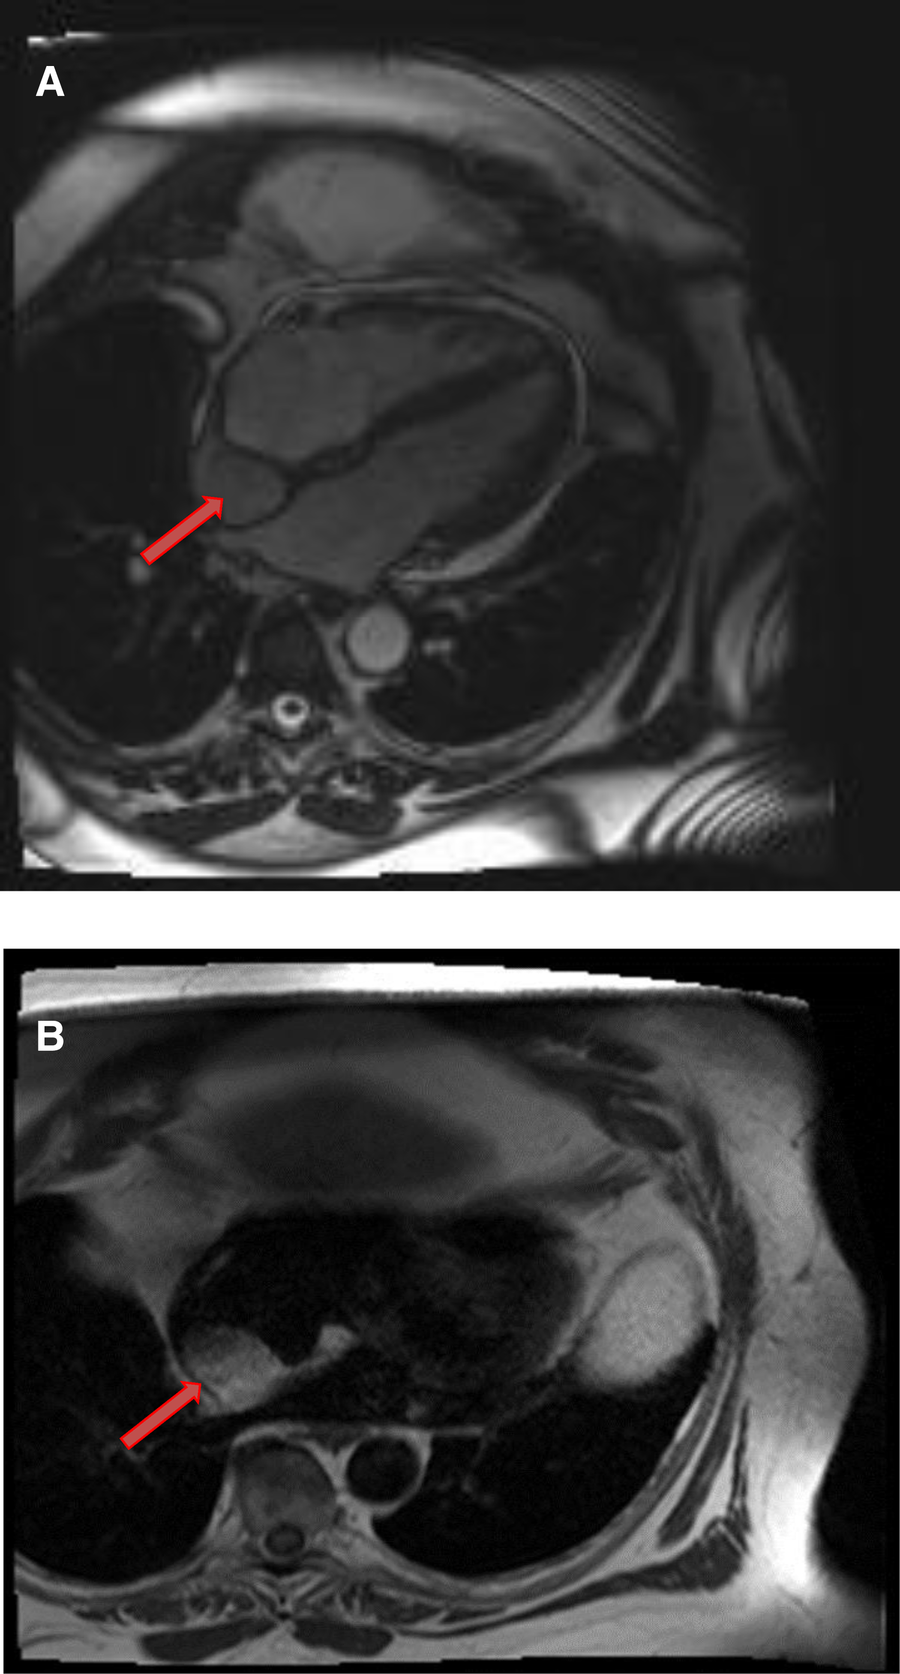

Cardiac paragangliomas are rare hyper-vascular masses that arise from the cardiac neuroendocrine cells (55). Patients are usually young and present with various symptoms of excessive catecholamine secretion. Surgical resection is often recommended, although it is challenging presumably due to their vascular nature and intimate relationship with the coronary arteries. On CMR, they are isointense to the myocardium on T1-weighted images and significantly hyperintense on T2 -weighted images (56). Due to high vascularity, they typically show uniform, intense enhancement during and after gadolinium contrast administration (Figures 11,12). Occasionally, they may show heterogeneous enhancement due to associated areas of hemorrhage and necrosis.

Figure 11

A 54-year-old male with right ventricular pheochromocytoma. (A) The mass is isointense on T1- weighted, dark blood, double inversion recovery fast spin echo images (red arrow). (B) The mass demonstrates peripheral hyper-vascularity with central areas of nonenhancement on first pass perfusion images (red arrow). (C) There is central enhancement of this mass on late gadolinium enhanced images (red arrow).

Figure 12

A 53-year-old male with inter-atrial septal pheochromocytoma. (A) The mass is bright on T2- weighted, dark blood, double inversion recovery fast spin echo images (red arrow). (B) This mass shows heterogeneous enhancement on late gadolinium enhanced images (red arrow).